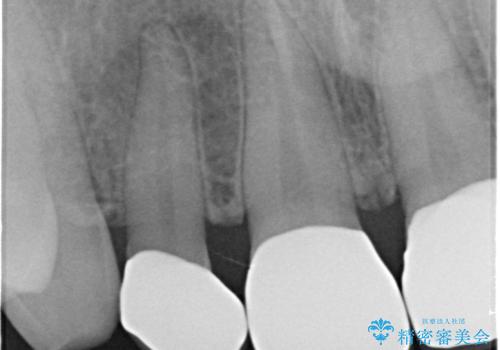

- 前歯の隙間を埋めたいとのことで来院された患者様です。

矯正治療とかぶせ物での治療どちらともご提案したところ、かぶせ物での治療をご希望されたためクラウンでの審美性回復を試みることとなりました。

今回のように、元の歯が小さすぎる場合は矯正治療での審美性回復が難しいことがあります。

形のイメージを反映させた仮歯を調整し、技工士さんと連携して製作したため口元に調和した非常に審美的なクラウンを装着することができました。